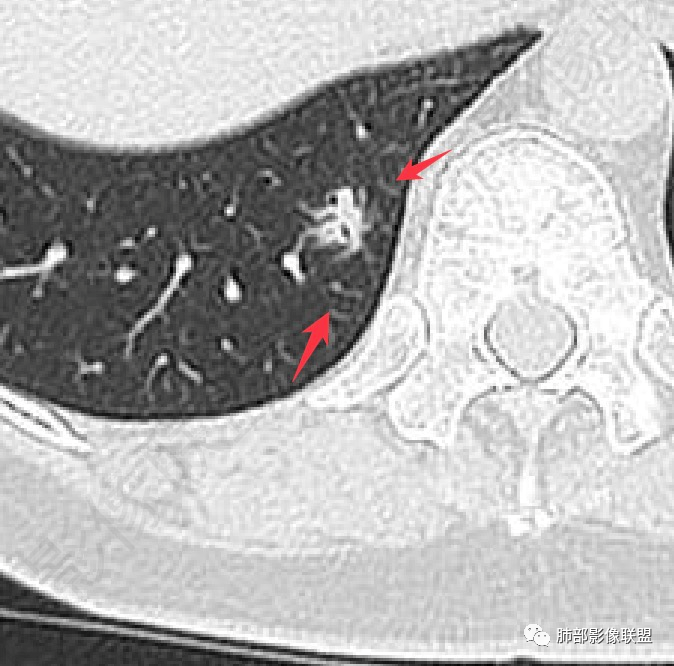

2. 首先定位。这个病变位于胸膜下、肺内病变没问题。请仔细看箭头所示的条索影,我感觉像小叶间隔。